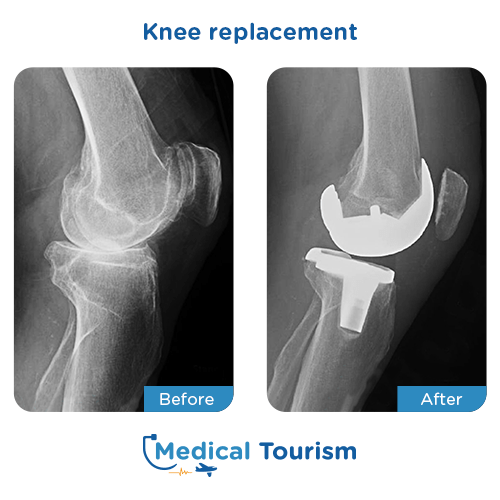

Before and after images

View before and after pictures from real patients.

Knee replacement before after